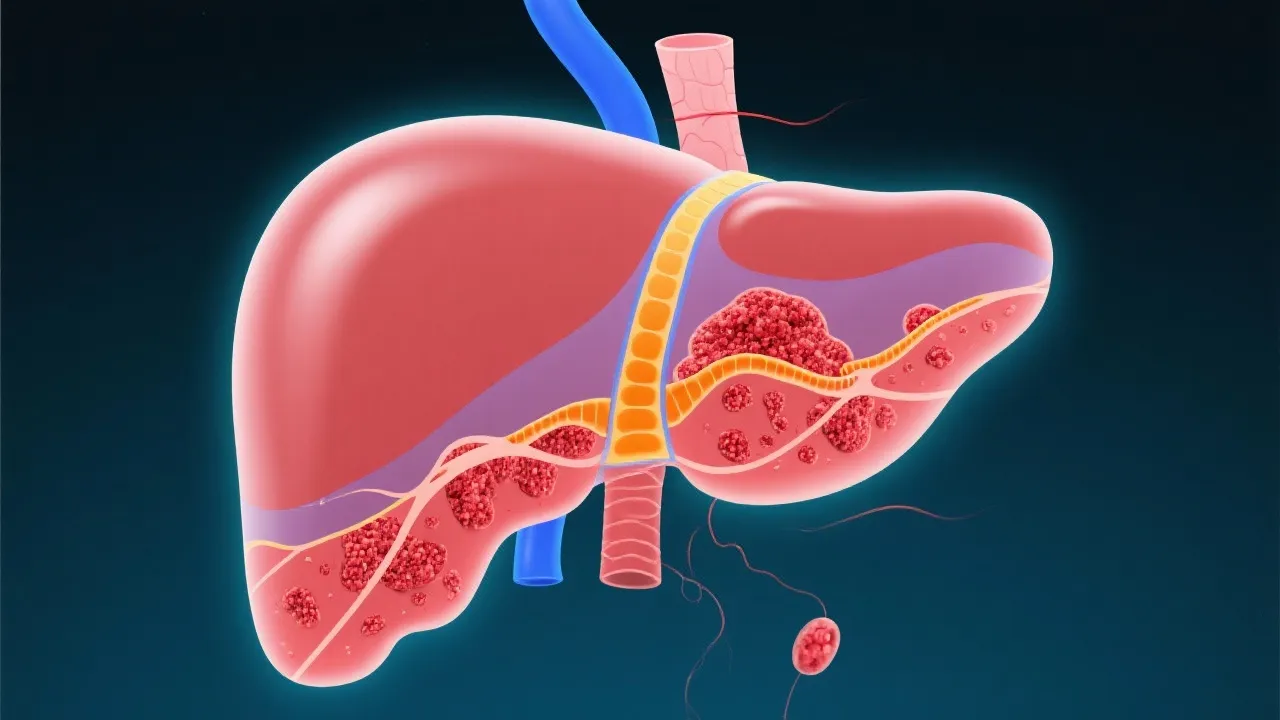

Non-alcoholic fatty liver disease (NAFLD) is increasingly linked to hepatocellular carcinoma (HCC), a primary liver cancer. This article delves into the complex relationship between NAFLD and HCC, exploring its implications for public health. It offers expert insights into diagnosis, management, and prevention strategies to address this growing challenge.

In recent years, the medical community has noticed significant links between non-alcoholic fatty liver disease (NAFLD) and hepatocellular carcinoma (HCC). As obesity and metabolic syndrome become more common globally, NAFLD has emerged as a predominant liver disorder, characterized by excessive fat in liver cells unrelated to alcohol consumption. Concurrently, HCC, the very common primary liver cancer, has started to manifest more frequently, demonstrating a potential epidemiological and pathological link to NAFLD. Recent studies suggest that the prevalence of HCC in patients with established NAFLD is rising, underlining the necessity for ongoing research into preventative measures and treatment modalities. Understanding the association between these two conditions is crucial for the development of effective screening protocols and strategies aimed at reducing morbidity and mortality rates associated with liver disease.

NAFLD encompasses a spectrum of liver conditions, from simple steatosis (fat accumulation) to non-alcoholic steatohepatitis (NASH), where inflammation and liver cell damage occur. If left unchecked, NASH can progress to cirrhosis and eventually HCC. NAFLD is often asymptomatic, which makes early detection challenging. Patients may remain unaware of the condition until significant liver damage has occurred. The growing understanding of NAFLD is vital, not just for individual patient care, but also for broader public health efforts aimed at combatting the rising obesity epidemic and associated metabolic disorders.

The pathogenesis of NAFLD-related HCC involves a complex interplay of genetic, metabolic, and inflammatory factors. Insulin resistance, oxidative stress, and the release of inflammatory cytokines contribute to liver fibrosis, cirrhosis, and ultimately, carcinogenesis. Due to the insidious nature of NAFLD, many patients may remain undiagnosed for years, allowing the disease to progress unchecked. The transition from NAFLD to NASH is particularly critical, as inflammation and fibrosis in the liver substantially increase the risk of developing HCC.

Several key mechanisms have been proposed to explain the progression from NAFLD to HCC. For instance, the accumulation of fat in liver cells triggers a cascade of metabolic dysregulation leading to cellular stress. This stress promotes inflammation and triggers the release of pro-inflammatory cytokines, such as TNF-alpha and interleukin-6, which contribute to liver cell injury. Excessive fat also leads to the formation of reactive oxygen species, causing oxidative damage to hepatocytes. Over time, the combination of these factors results in fibrosis, which is associated with an increased risk of malignancy.

Treatment options for HCC in NAFLD patients include surgical resection, liver transplant, and locoregional therapies like radiofrequency ablation. The choice of treatment depends on various factors, including tumor stage, liver function, and patient health. Resection is typically reserved for those with single tumors and preserved liver function, while liver transplantation is an option for patients with advanced disease and significant cirrhosis.

Locoregional therapies, such as radiofrequency ablation and transarterial chemoembolization (TACE), provide alternatives for patients who are not candidates for surgery. These approaches aim to reduce tumor burden and improve survival rates. Systemic therapies, such as tyrosine kinase inhibitors (e.g., sorafenib and lenvatinib) and immunotherapy, are also emerging in managing advanced-stage HCC. The current landscape of HCC treatment is rapidly evolving, with ongoing clinical trials designed to explore combination therapies and novel agents that can enhance treatment efficacy.